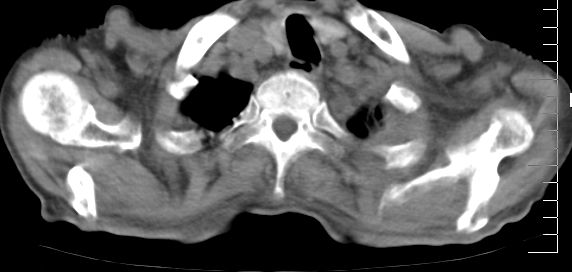

标题: CT10141:男、84岁,咳嗽、咯血1年。 [打印本页]

标题: CT10141:男、84岁,咳嗽、咯血1年。

1左侧胸腔积液并包裹2心包积液3左下肺癌?建议支纤镜检。

支持左侧中央型肺癌伴下叶肺不张\\纵隔淋巴结转移.左侧包裹性胸腔积液\\心包积液.左侧少量胸腔积液..慢性支气管炎伴部分间质纤维化.

支持:左侧中央型肺癌伴下叶肺不张\\纵隔淋巴结转移.左侧包裹性胸腔积液\\心包积液.左侧少量胸腔积液..慢性支气管炎伴部分间质纤维化.另:支气管分支根部明显阻塞 狭窄,内膜凸凹不平,提示内膜增生物。

左肺中心性肺癌并肺不张,同侧 胸膜及心包转移,左肺癌性淋巴管炎

左侧中心型肺癌,左侧胸腔积液部分包裹,心包积液,肿膈淋巴结显示。

咯血病史较长,左肺下叶实变,体积未明显缩小,隐约可见血管影及坏死阴影,双肺门及纵隔淋巴结增大,心包增厚积液,纵隔右移位,单侧胸腔积液,首先考虑:大叶型肺泡癌伴纵隔心包转移。

左下中央型肺癌伴阻塞性不张,肺炎,左侧包裹性胸腔积液\\心包积液

左肺中心性肺癌并左肺下叶肺不张,纵隔淋巴转移、同侧胸腔及心包积液(转移)。